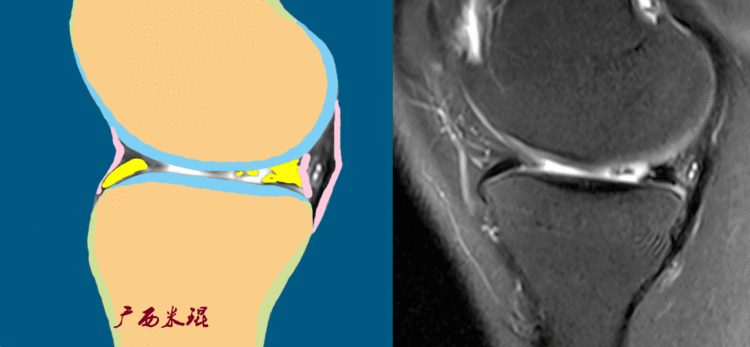

半月板损伤的mri诊断基础

图片尺寸750x347